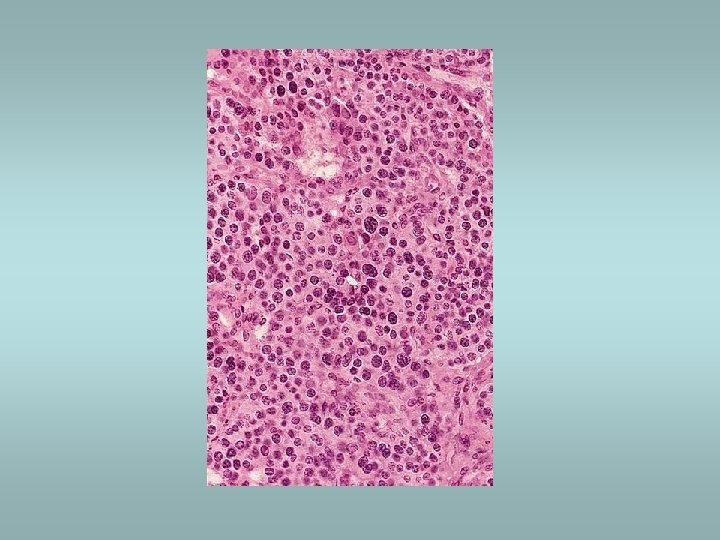

Adrenal medulla Phaeochromocytoma ü Catecholamine production – hypertension ü 85% in medulla (extra-adrenal tumors designated paragangliomas) ü Sporadic (90%) or associated with familial syndromes (MEN, von Hippel-Lindau, von Recklinghausen) ü Histologically – pleomorphism, mitotic activity - however there are no reliable histological predictors of malignancy!! ü Only criterion of malignancy – metastasis Other tumors – neuroblastoma, ganglioneuroma